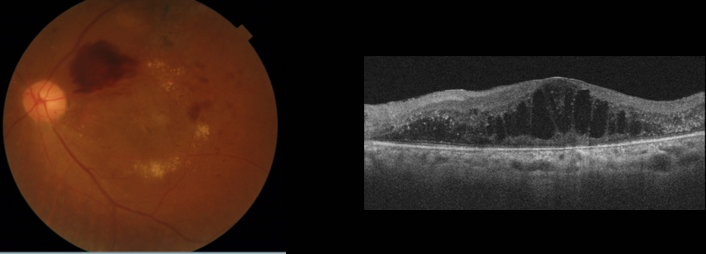

糖尿病黄斑症

黄斑は網膜の中心にあり、物を見るために最も重要なところです。黄斑付近に血管瘤ができたり、血液成分がしみだしたりして、黄斑にむくみができた状態を糖尿病黄斑症と言います。単純網膜症の段階でも黄斑症が出ると視力が落ちてしまいます。